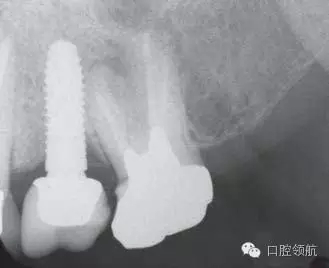

口內(nèi)檢查可見上部修復(fù)體有微動(dòng),沒有發(fā)現(xiàn)周圍黏膜組織的異常(圖1)。 X線影像可以看到種植體的周圍有一定程度的骨吸收但未發(fā)現(xiàn)周圍軟組織的異常(圖2)。考慮是基臺(tái)松動(dòng)的可能性較高。向患者說(shuō)明松動(dòng)的原因,需要去除上部修復(fù)體后再度擰緊固定基臺(tái)螺絲。因上部修復(fù)體的固定使用的是臨時(shí)粘接劑。先嘗試使用去冠器,但未能去除。

圖2 X線攝影像上可以看到種植體的周圍有一定程度的骨吸收但未發(fā)現(xiàn)有周圍軟組織的異常(圖2)??紤]基臺(tái)松動(dòng)的可能性較高。